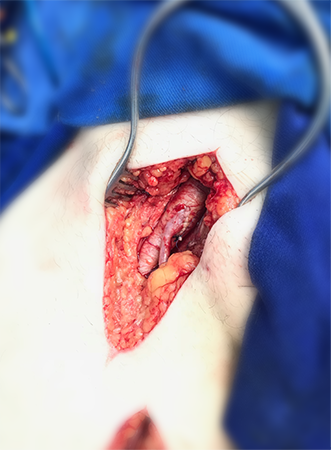

Endarterectomia de Carótidas

A deposição de colesterol e cálcio na parede das artérias carótidas pode levar ao Acidente Vascular Cerebral Isquêmico, que é a terceira causa mais importante de morte por doença na população. A partir de um determinado grau de estreitamento do vaso, está indicada a correção, seja através de angioplastia com colocação de stent, ou da remoção completa da placa de ateroma pela cirurgia de Endarterectomia. Apesar da Angioplastia com stent representar um avanço no tratamento desta doença, a cirurgia continua sendo a principal forma de correção para a maioria dos pacientes. Feita com anestesia geral, através de uma incisão no pescoço, o cirurgião abre a artéria doente, e remove toda a placa que provoca o estreitamento. Normalmente são necessários dois dias de internação hospitalar e o paciente estará apto a retomar suas atividades diárias imediatamente.